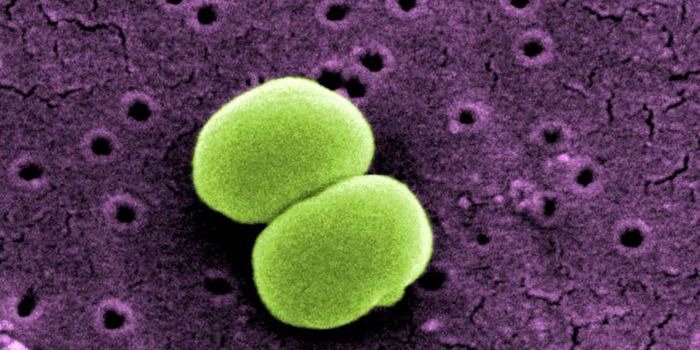

NOV 02, 2021MicrobiologySyphilis is on the rise worldwide, and it's killing infants. The disease is a leading cause of stillbirth worldwide, acc ...